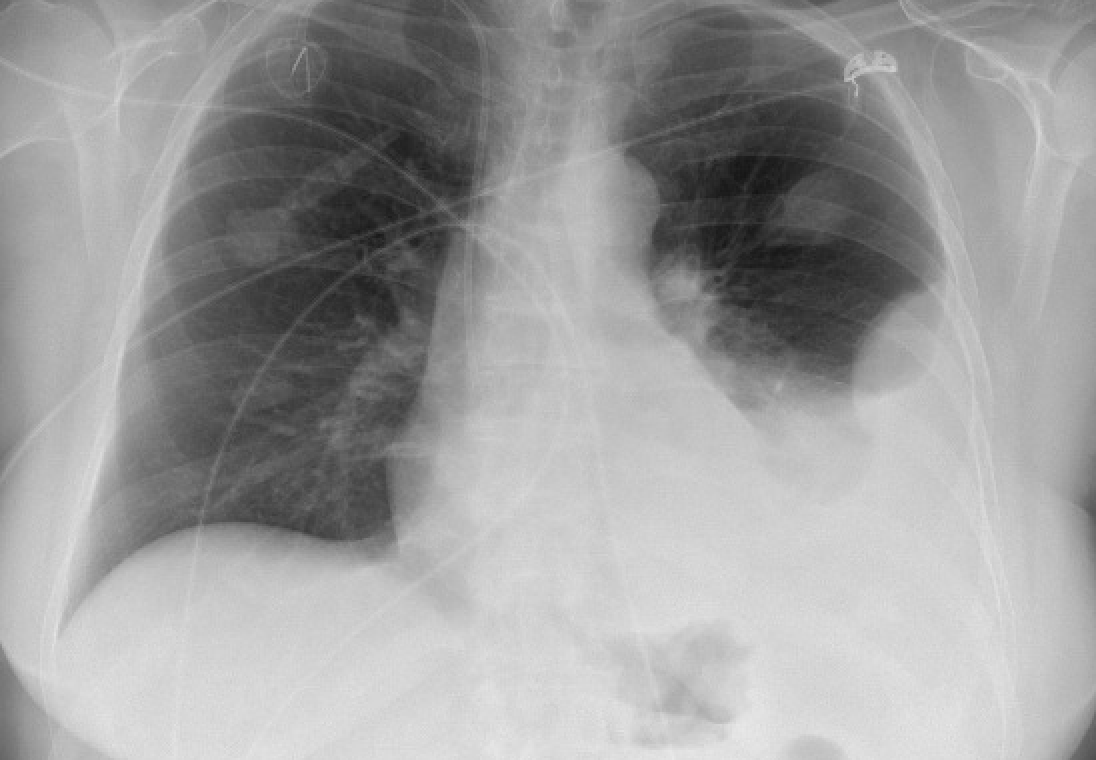

Hi all - quick procedural #IMPOCUS case for y'all today. We have a 75 yo M w metastatic lung CA, consulted for therapeutic thoracentesis. Initial CXR here

1/